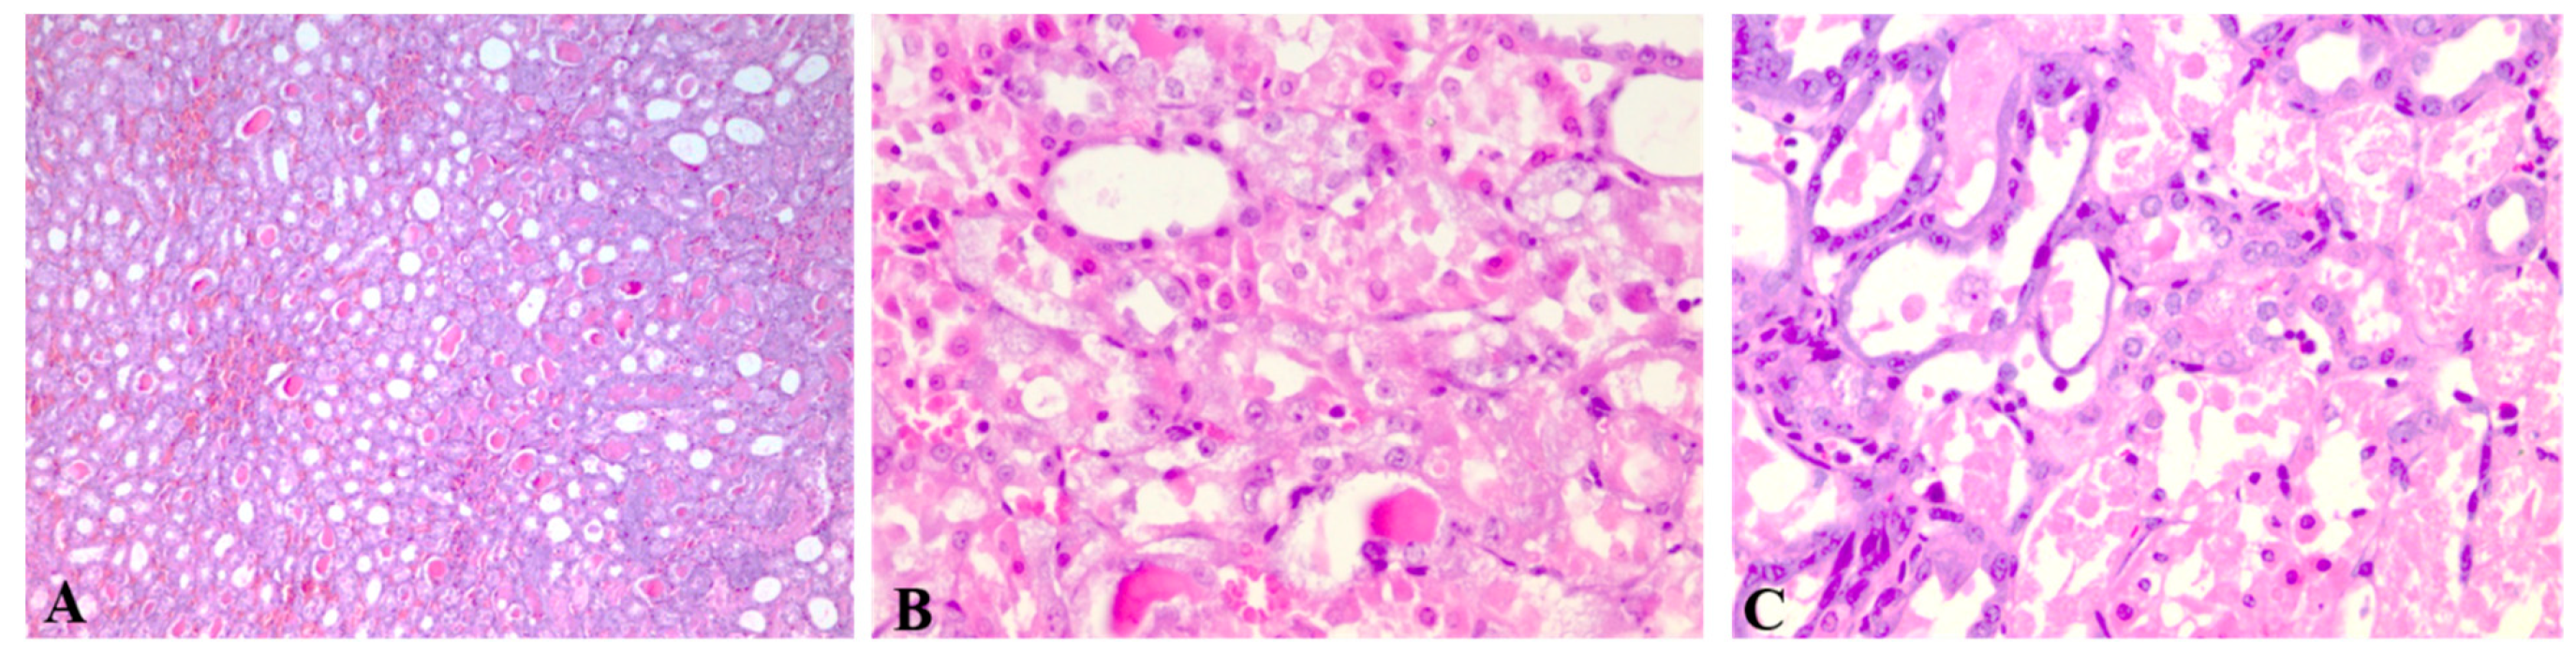

3.3. Kidney Histology Examination

| Group | Score |

|---|---|

| Control | 0 |

| GE1 | 0 |

| GE2 | 0 |

| Cis | 2 |

| GE1 + Cis | 2 |

| GE2 + Cis | 3 |

| GE1 + Cis + GE1 | 1 |

| GE2 + Cis + GE2 | 3 |